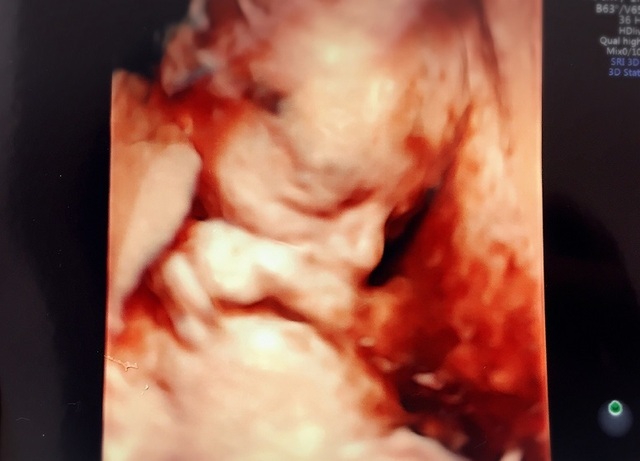

19週1日(19w1d・男の子)|きうらよしこ さん(35歳)

エコー写真撮影時のエピソード:

初めて4Dエコーで我が子を見ることができました。普通のエコーに比べ、鮮明に顔を見ることができ、更に愛しく思えたのを記憶しています。悪阻がきつかったですが、時折写真を眺め、悪阻があるってことは子どもが元気に育っている証拠なんだなぁ等気持ちが前向きになり、どんなお顔なのかな?等話しかけたりしていました。主人も写真を見返しては、どっちに似てるんだろうなぁと嬉しそうに話していました。食事面に関しては、幸い食べ物は何でも食べれたので、あまり神経質にならず好きなものを口にしていました。ですが、出来るだけ自炊をし、赤ちゃんに良いものをと色々ネットで調べて作ったりしました。自分が口にしたものがそのまま我が子へ繋がってるんだなぁ、しっかり栄養とってね等話しかけたりもしてましたね。